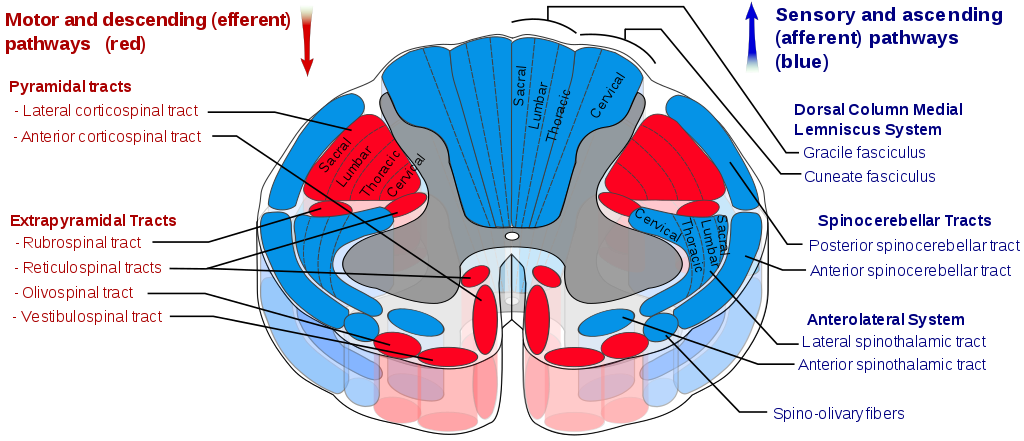

A spinal cord stimulator is an implanted device under battery power. Doctors use these ‘pain pacemakers’ as they call them to treat certain pain conditions. Basically, they use them to send electrical signals to select areas of the spinal cord. The commonest use is relieving suffering among patients with failed back surgery syndrome.